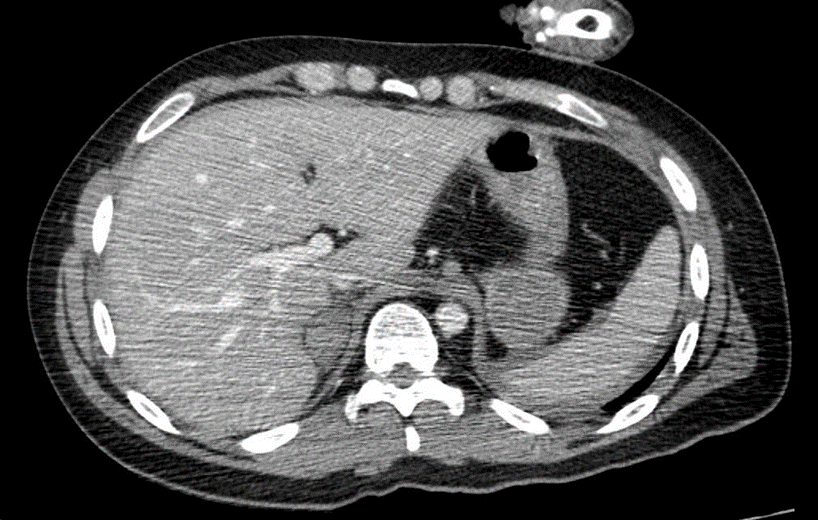

Figura 2: radiografia da pelve.

Paciente do sexo masculino, 24 anos, da entrada no pronto-socorro do Conjunto Hospitalar de Sorocaba (CHS) dia 01/04/2025, vítima de colisão moto x anteparo fixo, apresentando fratura exposta de fêmur esquerdo, rotação externa de membro inferior direito com fratura exposta de fêmur direito distal e desalinhamento de antebraço esquerdo.

C: Tempo de preenchimento capilar <3 segundos, frequência cardíaca (FC) de 126 batimentos por minuto, pressão arterial (PA) 97×71 mmHg, bulhas rítmicas, normofonéticas em dois tempos, abdome globoso, flácido, indolor à palpação com fast negativo, sínfise púbica fechada, pelve estável.

Frente ao caso, como conduta inicial foram solicitadas radiografias de tórax e pelve no leito, iniciada expansão volêmica com 500 mL de Ringer lactato (apresentando resposta com melhora da PA: 128×71 mmHg e FC 105 bpm), radiografia de fêmur bilateral, joelho bilateral, perna bilateral, braço e antebraço esquerdo, tomografias de crânio, face, coluna cervical, torácica e lombar, tórax, abdome e pelve, sendo as duas últimas com contraste. Além dos exames de imagem, foram solicitados também exames de laboratório.